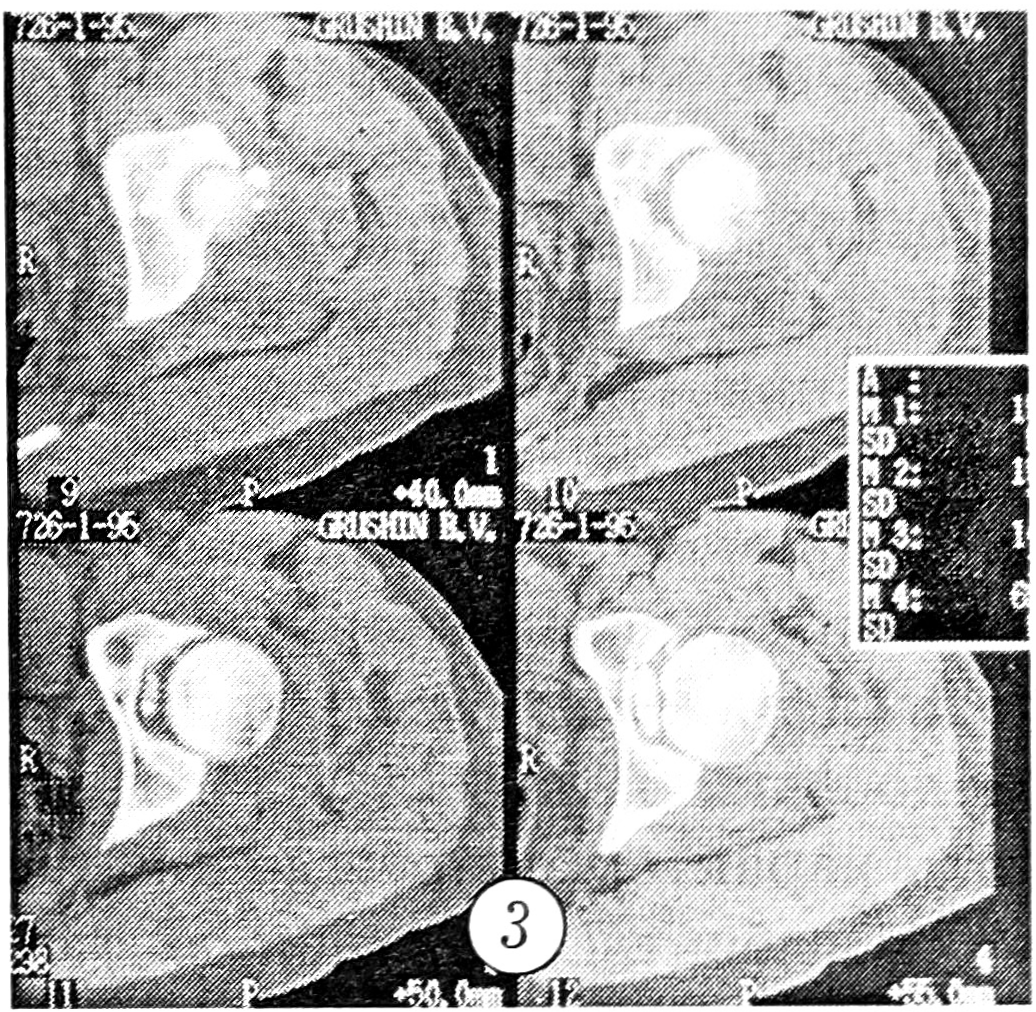

Больная Л., 23 лет, на рентгенограмме в стандартной переднезадней проекции выявлен перелом лонной и седалищной костей справа (рис. 4). При компьютерной томографии, помимо этого, обнаружены оскольчатый перелом боковой массы крестца справа (рис. 5, а) и отрыв костного фрагмента в области лонного сочленения (рис. 5, б).

Рис. 4. Рентгенограмма больной Л. в стандартной переднезадней проекции.